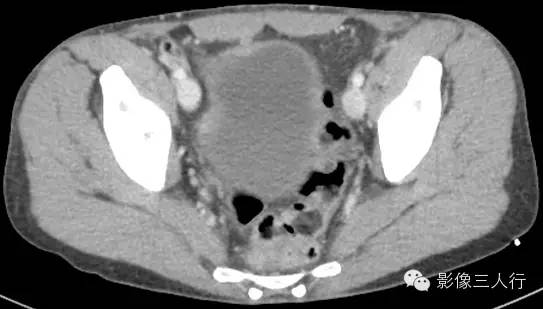

延盲肠层面向下延续能看到腹股沟管走行区可见到管状的阑尾影像,腔内可见气体密度,阑尾壁无增粗,周围无明显渗出。